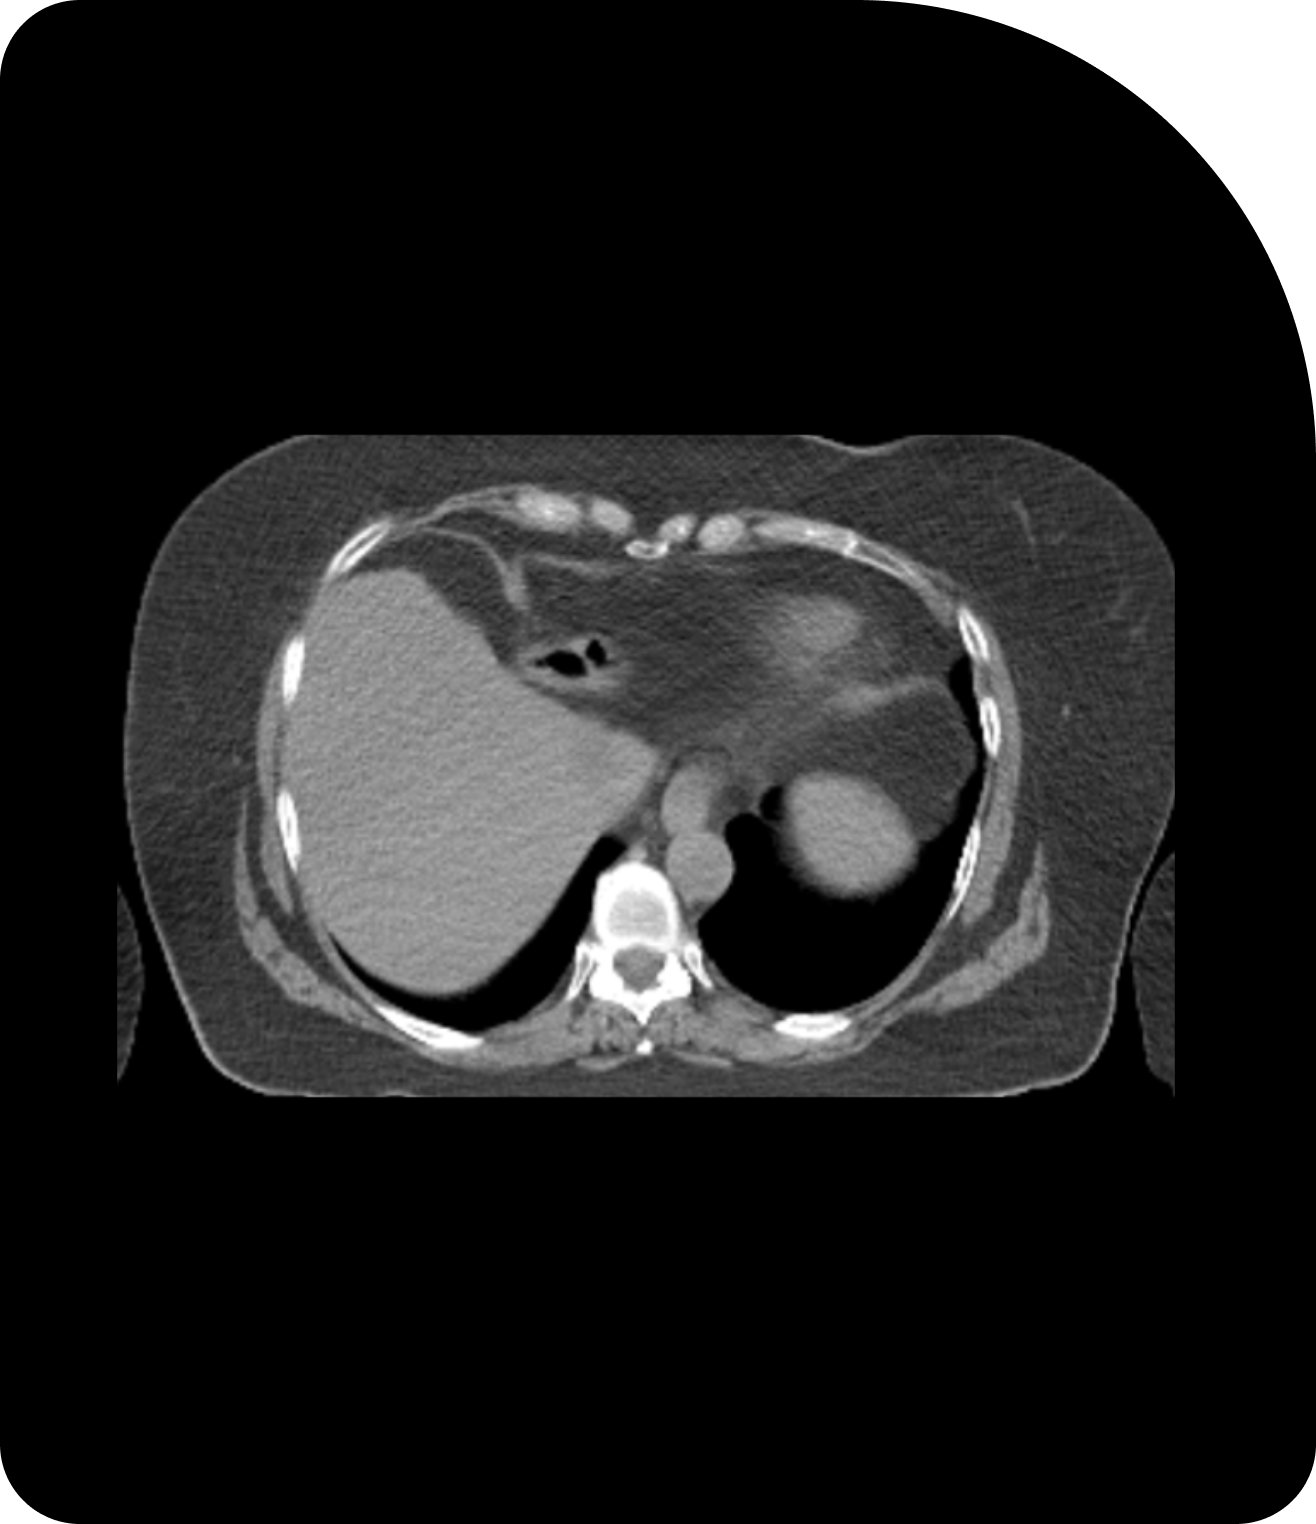

Des images plus claires signifient un ciblage plus précis. Comparez la tomodensitométrie (TDM), la tomodensitométrie volumique à faisceau conique (CBCT) et l’imagerie par résonance magnétique (IRM) pour constater la différence.

TDM

L'imagerie standard fournit une vue de référence pour la planification du traitement.